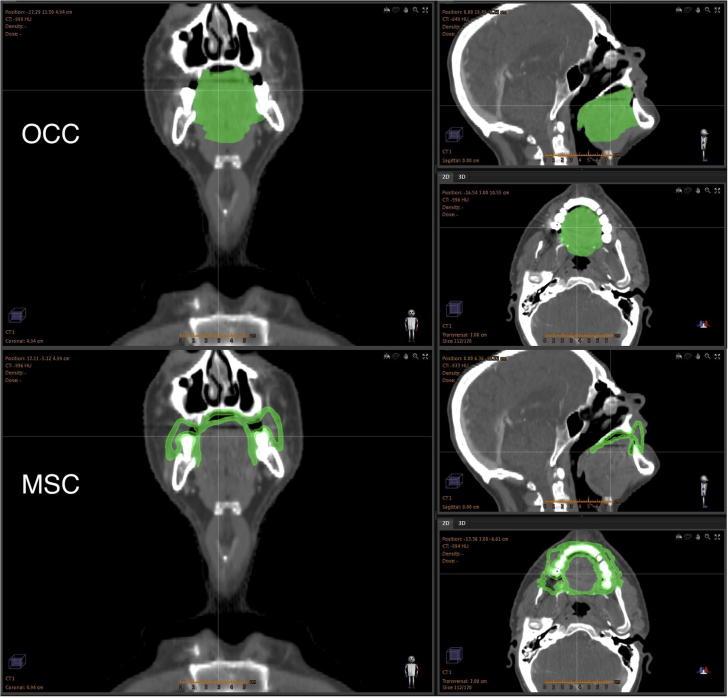

There is currently no standard method for delineating the oral mucosa and most attempts are oversimplified. A new method to obtain anatomically accurate contours of the oral mucosa surfaces was developed and applied to 11 patients. This is expected to represent an opportunity for improved toxicity modelling of oral mucositis.